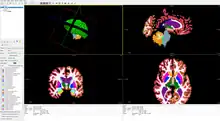

FreeSurfer is brain imaging software originally developed by Bruce Fischl, Anders Dale, Martin Sereno, and Doug Greve.[2] Development and maintenance of FreeSurfer is now the primary responsibility of the Laboratory for Computational Neuroimaging[3] at the Athinoula A. Martinos Center for Biomedical Imaging. FreeSurfer contains a set of programs with a common focus of analyzing magnetic resonance imaging (MRI) scans of brain tissue. It is an important tool in functional brain mapping and contains tools to conduct both volume based and surface based analysis.[4] FreeSurfer includes tools for the reconstruction of topologically correct and geometrically accurate models of both the gray/white and pial surfaces, for measuring cortical thickness, surface area and folding, and for computing inter-subject registration based on the pattern of cortical folds.

The FreeSurfer processing stream is controlled by a shell script called recon-all.[10] The script calls component programs that organize raw MRI images into formats easily usable for morphometric and statistical analysis. FreeSurfer automatically segments the volume and parcellates the surface into standardized regions of interest (ROIs). Freesurfer uses a morphed spherical method to average across subjects for statistical (general linear model) analysis with the mri_glmfit [11] tool. FreeSurfer contains a range of packages allowing a broad spectrum of uses, including:

- FreeView, a tool to visualize FreeSurfer output, which can also display common MRI image formats[12]